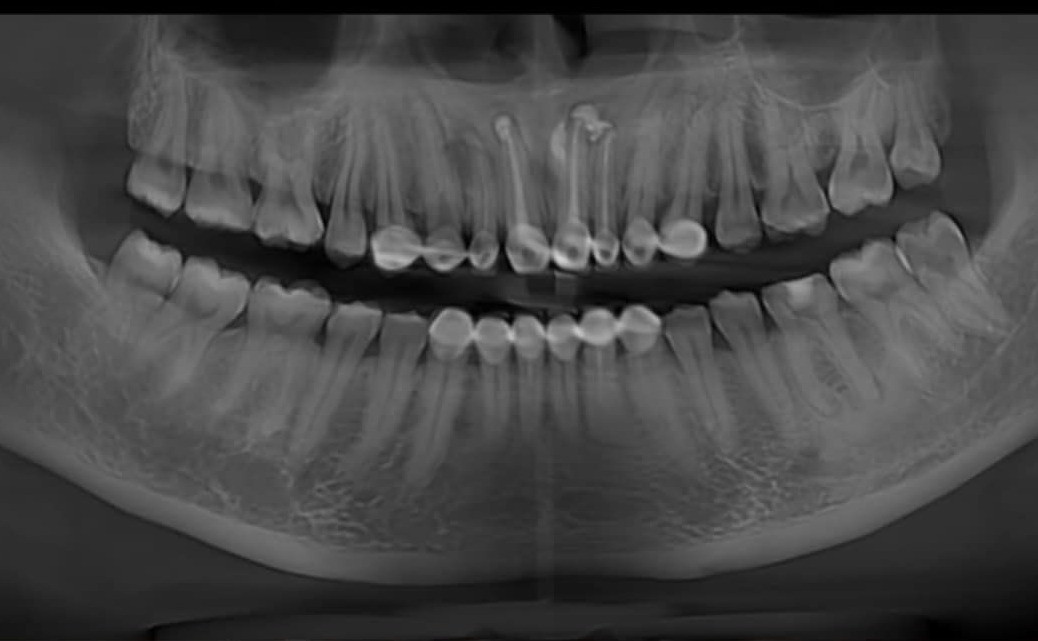

Bác sĩ phát hiện vùng răng cửa hàm trên của chị có khối phồng kích thước 3x2cm, sờ căng tức, có dấu hiệu bóng nhựa, răng giả từ răng 14-24 (8 chiếc răng). Bác sĩ chẩn đoán bệnh nhân bị nang xương hàm, chỉ định phẫu thuật cắt nang răng vùng cửa hàm trên.

Bác sĩ chuyên khoa I Lê Thị Hà, Trưởng khoa Răng Hàm Mặt, Bệnh viện đa khoa tỉnh Bắc Giang, cho biết nang là một hốc bệnh lý trong xương hàm, có chứa dịch loãng hoặc nửa loãng hoặc khí, được lót bằng lớp tế bào biểu mô nhưng không phải luôn luôn có.